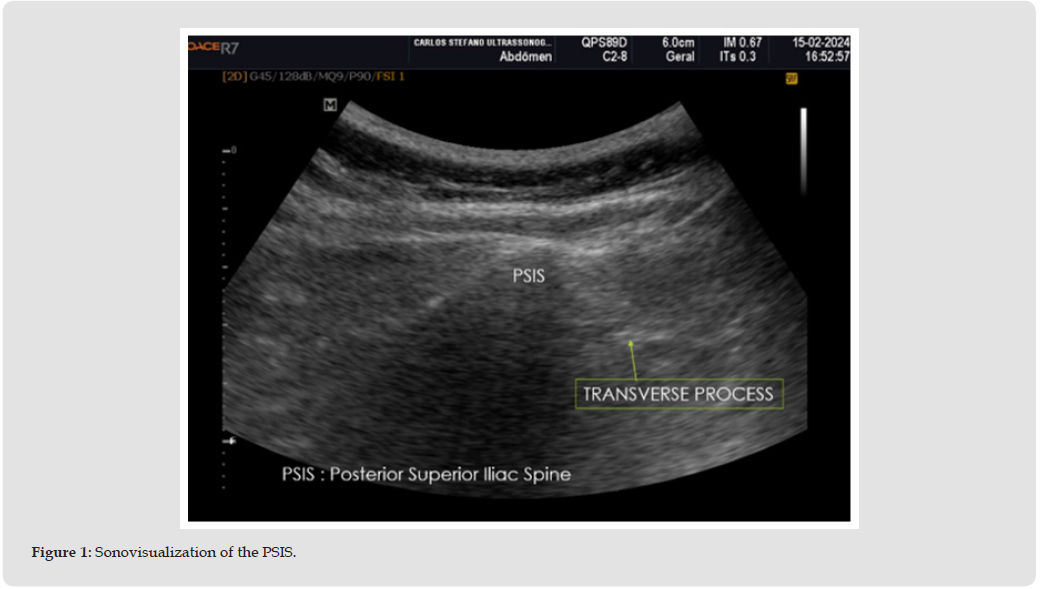

With the patient in the prone position, antisepsis of the lumbar region and hip is performed, followed by the placement of sterile drapes. The posterosuperior iliac spine (PSIS) is identified by ultrasonography, using a convex transducer to define the anatomical target. A local anesthetic is used to numb the skin and periosteum at the site of marrow collection. Lidocaine or another local anesthetic may be used if the patient has no history of adverse reactions to the drug. Complete local anesthesia, which avoids discomfort during the procedure, is ensured by waiting for adequate time after administration (Figure 1). The anesthetic used is usually prepared using 5 mL of sterile 2% lidocaine hydrochloride with 4 mL of normal saline and 1 mL of sterile 8.4% sodium bicarbonate solution (1 mEq/mL) in a 10 mL plastic syringe fitted with a 1-1/2-inch 22-gauge needle. Packing lidocaine with sodium bicarbonate improves pain perception from local anesthesia, which is usually caused by the acidity of lidocaine. This solution is applied intradermally, forming a small 5mm papule, through which the larger needles will be inserted to anesthetize the subsequent anatomical planes until it reaches the surface of the periosteum (Figure 2). After ultrasound identification of the PSIS, the needle is guided to the periosteum, where anesthetic infiltration with 1% lidocaine is performed for periosteal hydro dissection.

Ultrasound is used to identify PSIS accurately. During the scan, the probe is positioned over the patient’s skin, and the image generated clearly shows the bony bulge. The visual identification of the PSIS through ultrasonography ensures accurate and safe puncture, minimizing risks and increasing the effectiveness of bone marrow aspirate collection. After the PSIS is identified, the area is marked and prepared. The puncture is performed with a suitable needle, which is inserted through the skin and subcutaneous tissue until it reaches the bone marrow. The continuous use of ultrasound during needle insertion ensures that the needle stays on the correct path and penetrates the bone marrow accurately. The use of ultrasound significantly improves the accuracy in locating the PSIS. This visualization allows for an exact puncture and minimizes the margin of error. In addition, clear identification of anatomy by ultrasound reduces the risk of injury to surrounding tissues and nerves, making the procedure safer [42] (Figure 6). probe to locate the needle and perform the BMA collection by sound-guided approach.